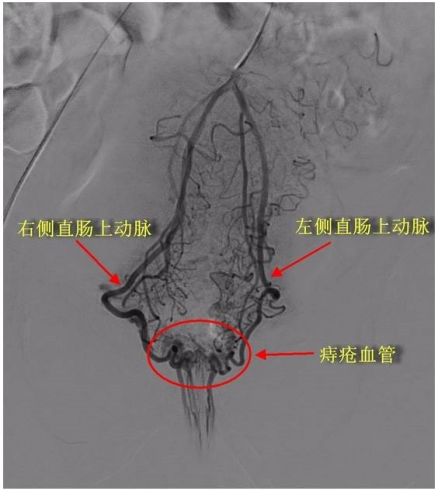

50岁的王某(化名)因工作繁忙、久坐不动且饮食不规律,长期受内痔困扰。尽管尝试多种药物治疗,但痔疮反复发作,严重影响生活质量。听说我院介入血管外科开展痔疮动脉栓塞术,遂来院就诊。我院介入血管外科团队对王某身体状况进行仔细评估后,决定采用介入手术治疗,通过数字减影血管造影(DSA)精准定位痔疮供血动脉,并进行栓塞治疗。术后第二天,患者就能下床活动,肛门坠胀感和便血症状显著改善,隔天康复出院。

术前 术后 "痔疮动脉栓塞术特别适合以出血为主要症状的II-III度内痔或混合痔患者,尤其适用于存在常规手术禁忌症或对传统外科手术顾忌重重的患者。"介入血管外科主任李俊杰介绍,该技术通过阻断痔疮供血使其逐渐萎缩,具有恢复快、疗效显著、住院时间短、患者痛苦少等优势,尤其适合高龄、体弱或合并其他基础疾病的患者。相较于传统手术,RAS术后疼痛程度较轻,护理流程相对简化,为痔疮患者提供了更微创、更舒适的治疗选择。